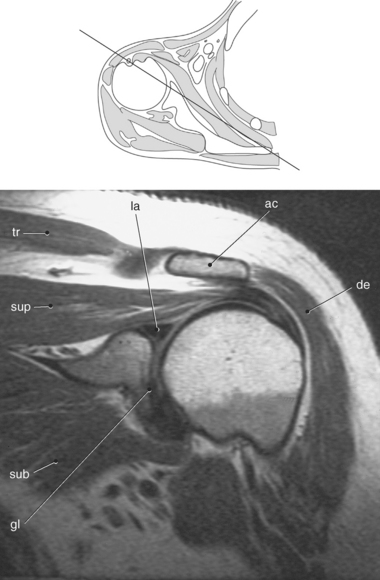

Figure 9.18 Coronal oblique, T1-weighted MR scan of shoulder with glenoid labrum.

Key: tr, Trapezius; la, labrum; ac, acromion; de, deltoid; gl, glenoid; sub, subscapularis; sup, supraspinatus.